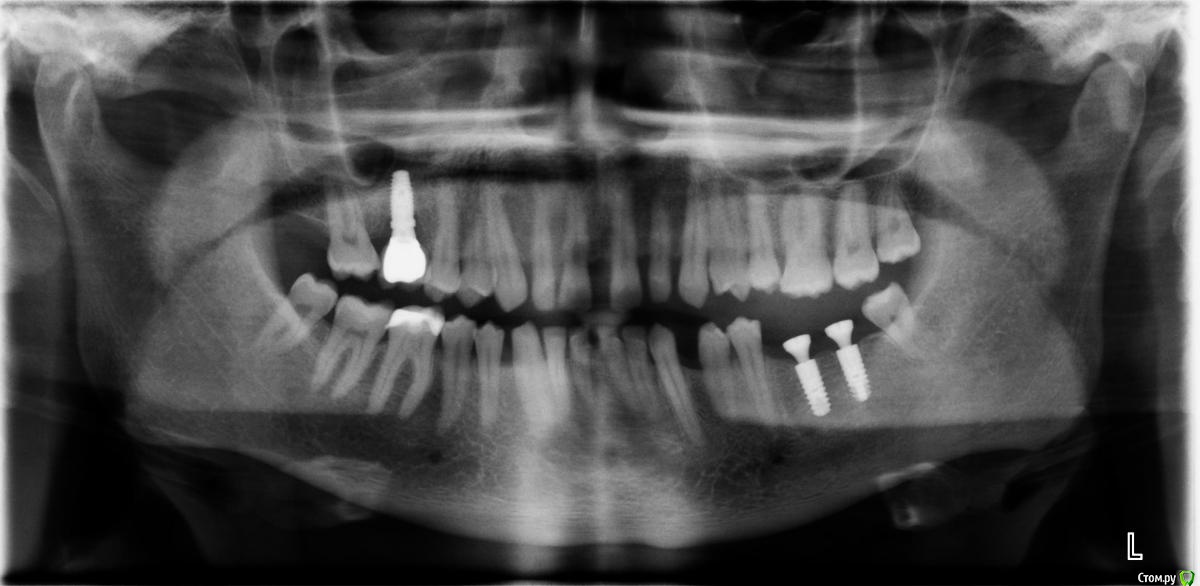

Arkasha18 Опубликовано 4 мая, 2019 Поделиться Опубликовано 4 мая, 2019 (изменено) 35 лет, мужчина.разъезжаются передние зубы все больше и больше, хочу выравнять, насколько ходил по специалистам, все советуют только брекеты.Но остается очень много вопросов по выбору специалиста, т.к. сейчас стоматологов очень много, я не могу выбрать хорошего специалиста, т.к. не разбираюсь в этом. Текущие специалисты меня не устраивают, т.к. допустили уже ряд ошибок которых не должно было быть. Прошу помощи как выбрать специалиста, какие вопросы ему задавать что бы понимать что он специалист хорошо разбирающийся, а не без опытный какой то.набросайте несколько вопросов какие можно задавать пожалуйста. - на например связанные с какими то технологиями, - процессом техническим - варианты брекет систем чем отличаются может что то спросить в общем не знаю..хочется задать вопросы и что бы было понятно кто передо мной, ленивый, знающий, или нет и т.п. если кто то посоветует в питере специалиста на севере города (коменда, старая деревня, пионерская) буду безмерно благодарен И второй вопрос у меня три импланта, верхний на коронке, нижние два без. соот-но придется их снимать? снимки прикрипляю Изменено 4 мая, 2019 пользователем Arkasha18 Ссылка на комментарий